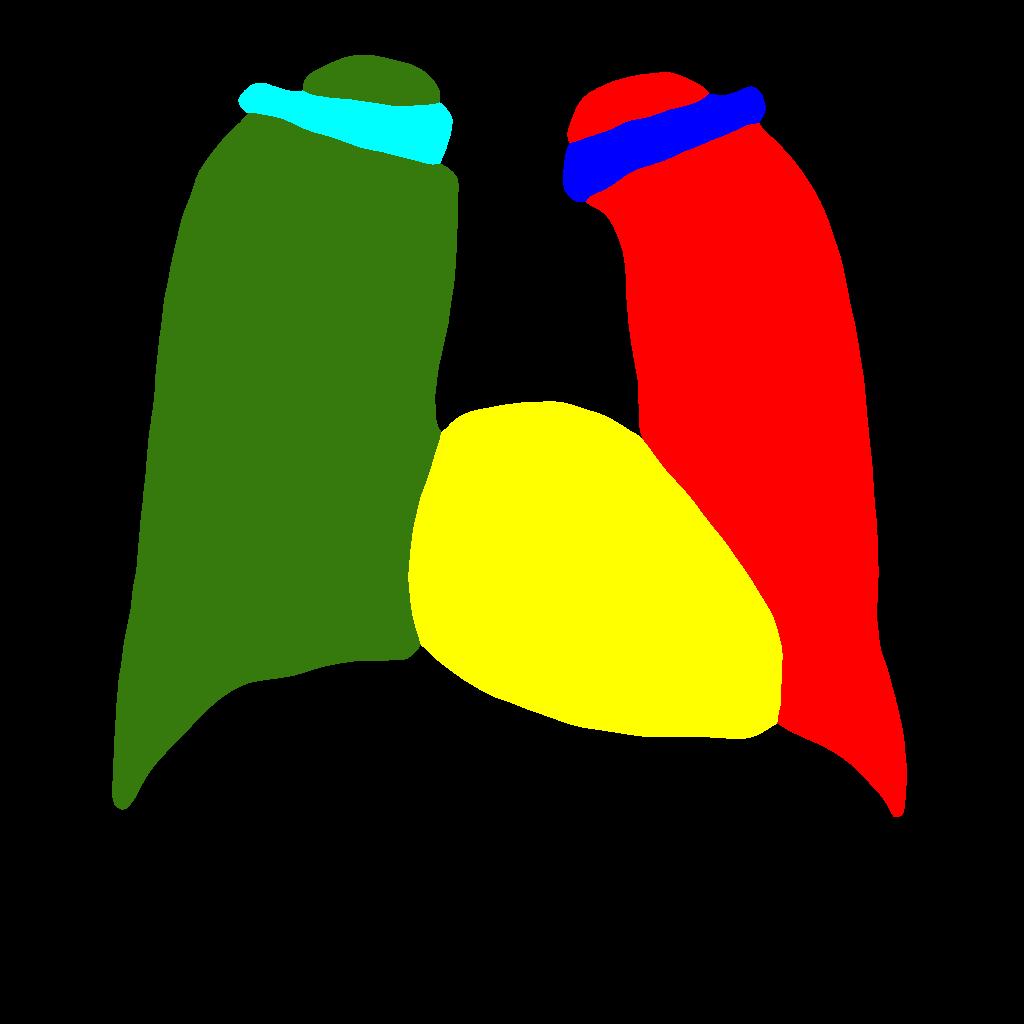

In this approach, the generation procedure is divided into two steps. The first one consists in generating the labels through a PGGAN, while, in the second, the translation from the label to the corresponding chest X–ray image is carried out, using Pix2PixHD (see Figure 2).